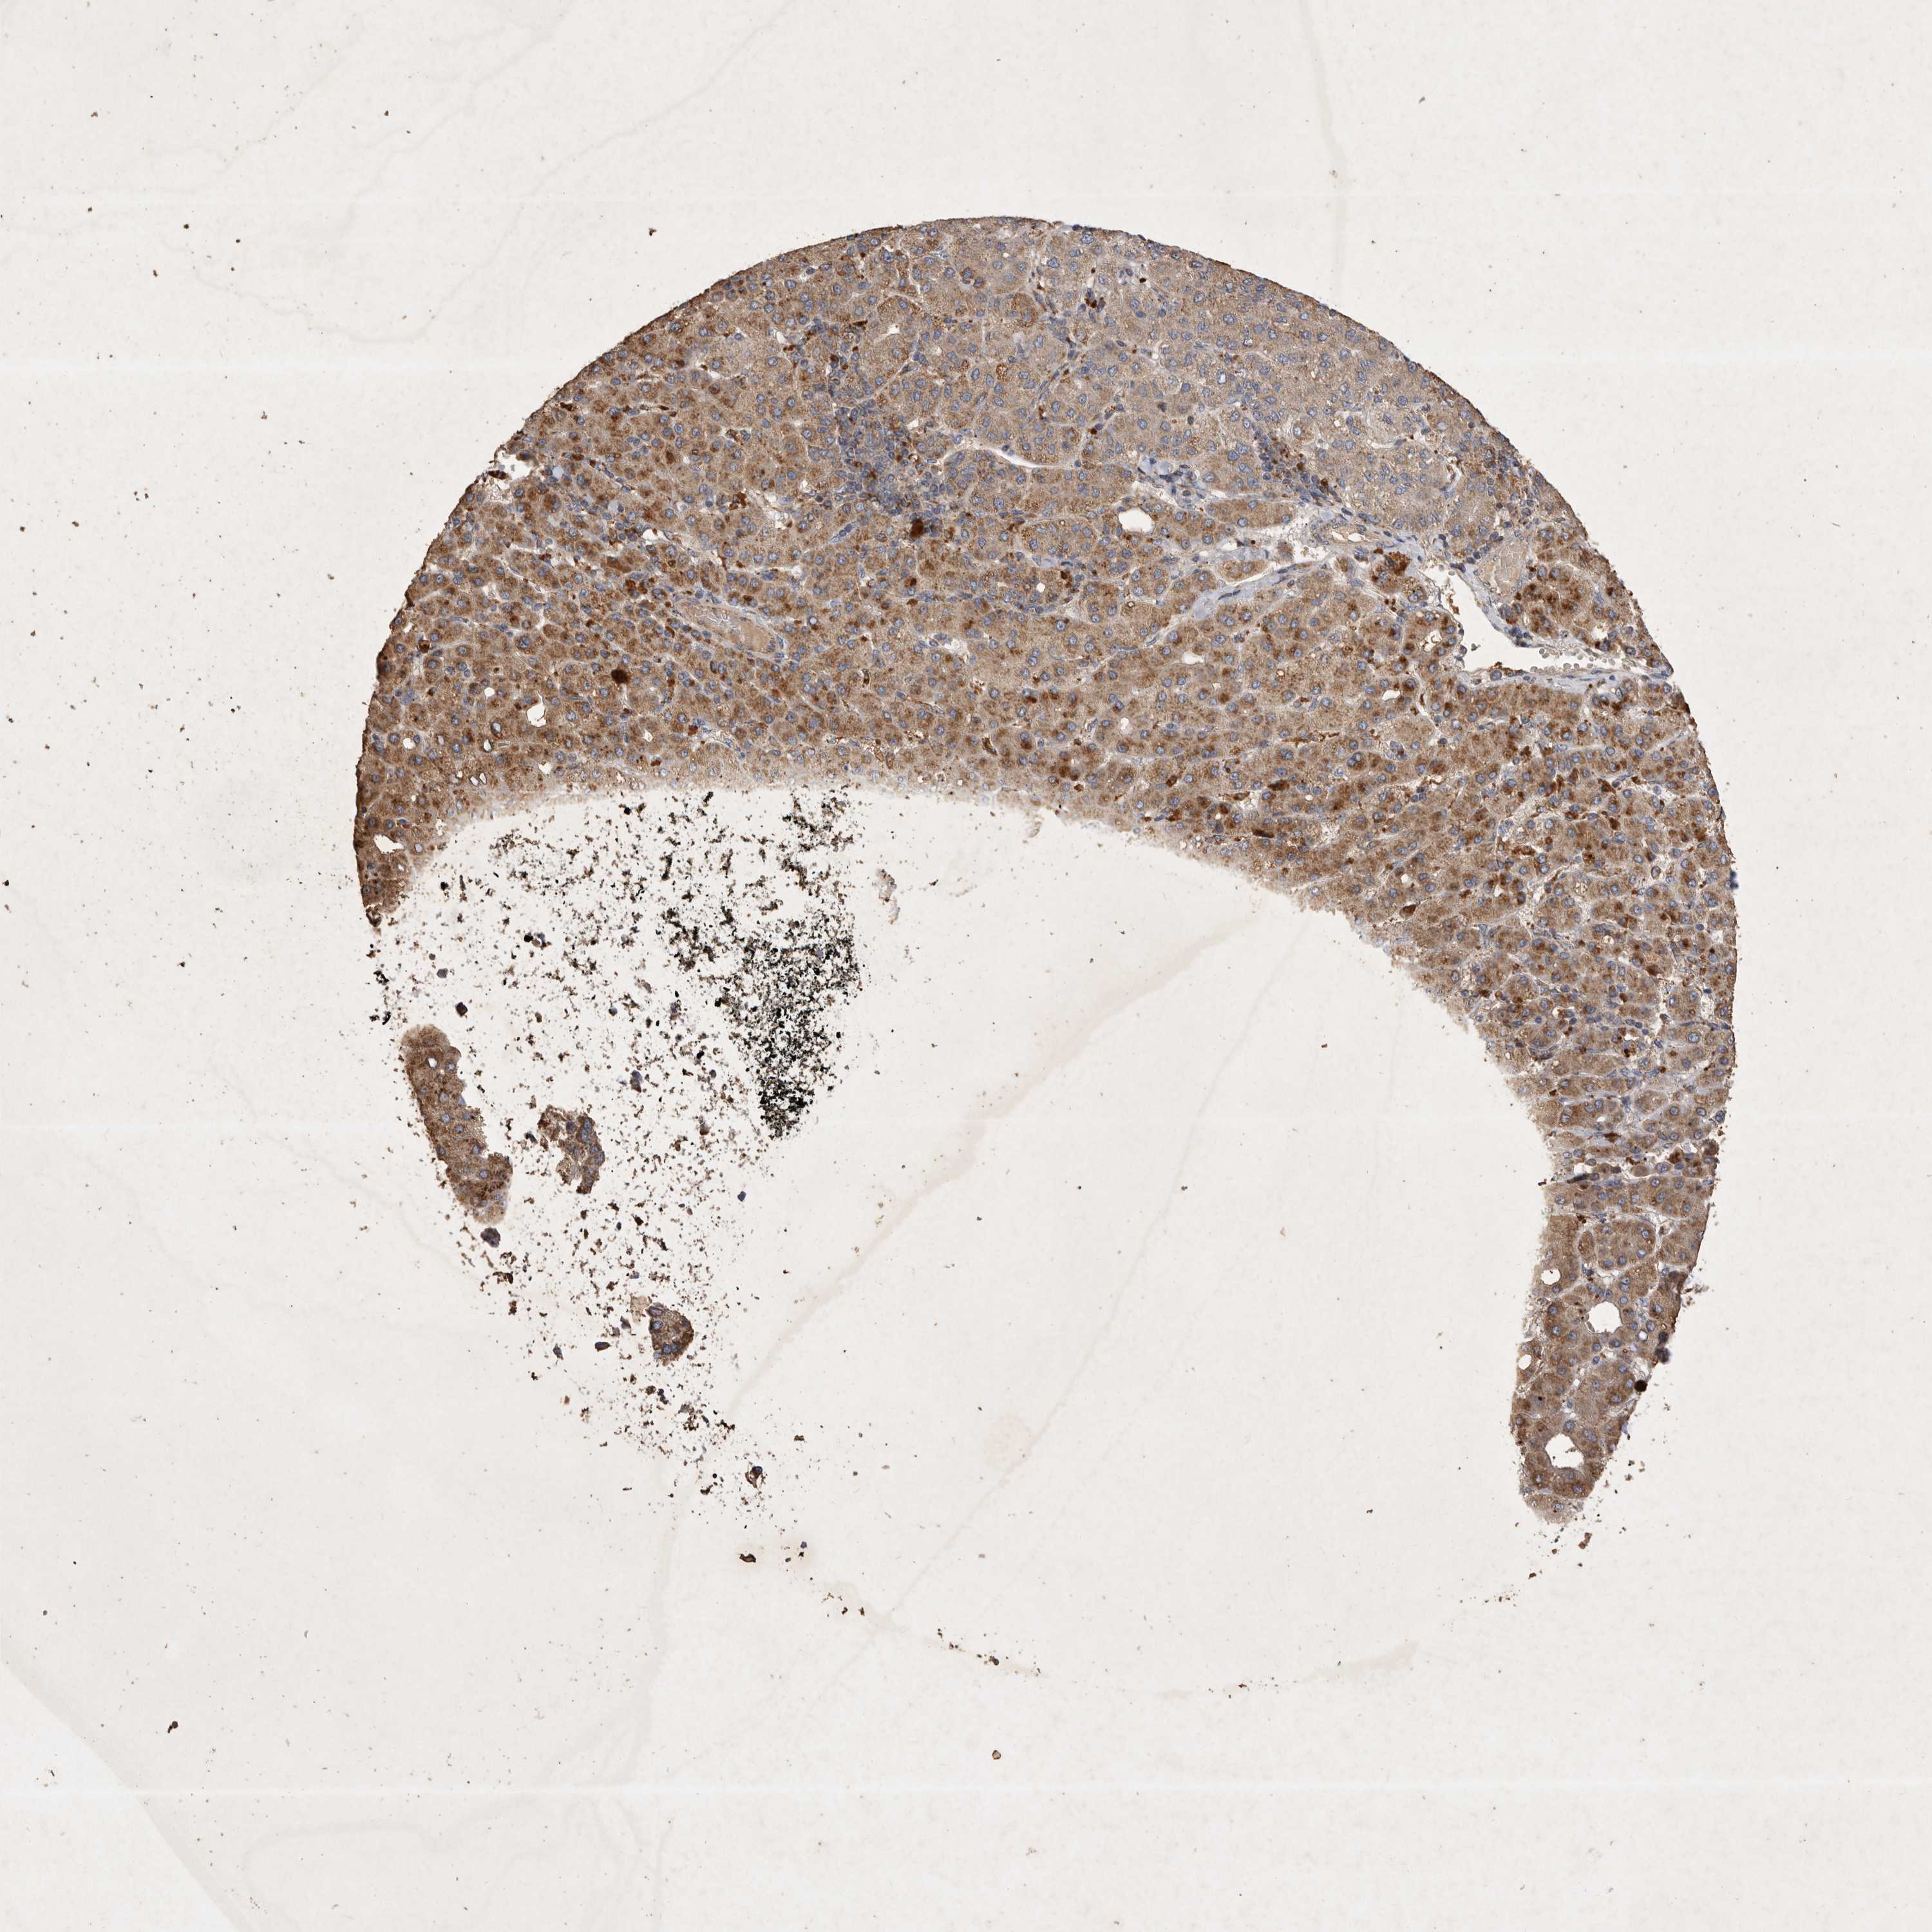

LIVER CANCER - Protein expressioni

A mouse-over function shows sample information and annotation data. Click on an image to view it in a full screen mode. Samples can be filtered based on level of antibody staining by selecting one or several of the following categories: high, medium, low and not detected. The assay and annotation is described here.

Note that samples used for immunohistochemistry by the Human Protein Atlas do not correspond to samples in the TCGA dataset.

Antibody stainingi

Antibody staining in the annotated cell types in the current human tissue is reported as not detected, low, medium, or high, based on conventional immunohistochemistry profiling in selected tissues. This score is based on the combination of the staining intensity and fraction of stained cells.

Each image is clickable and will lead to virtual microscopy that enables deeper exploration of all samples and also displays staining intensity scores, fraction scores and subcellular localization as well as patient and tissue information for each sample.

Antibody HPA024550

Antibody HPA027160

Staining

High

Medium

Low

Not detected

Intensity

Strong

Moderate

Weak

Negative

Quantity

>75%

75%-25%

<25%

None

Location

Nuclear

Cytoplasmic/membranous

Cytoplasmic/membranous,nuclear

Cholangiocarcinoma

Carcinoma, Hepatocellular, NOS